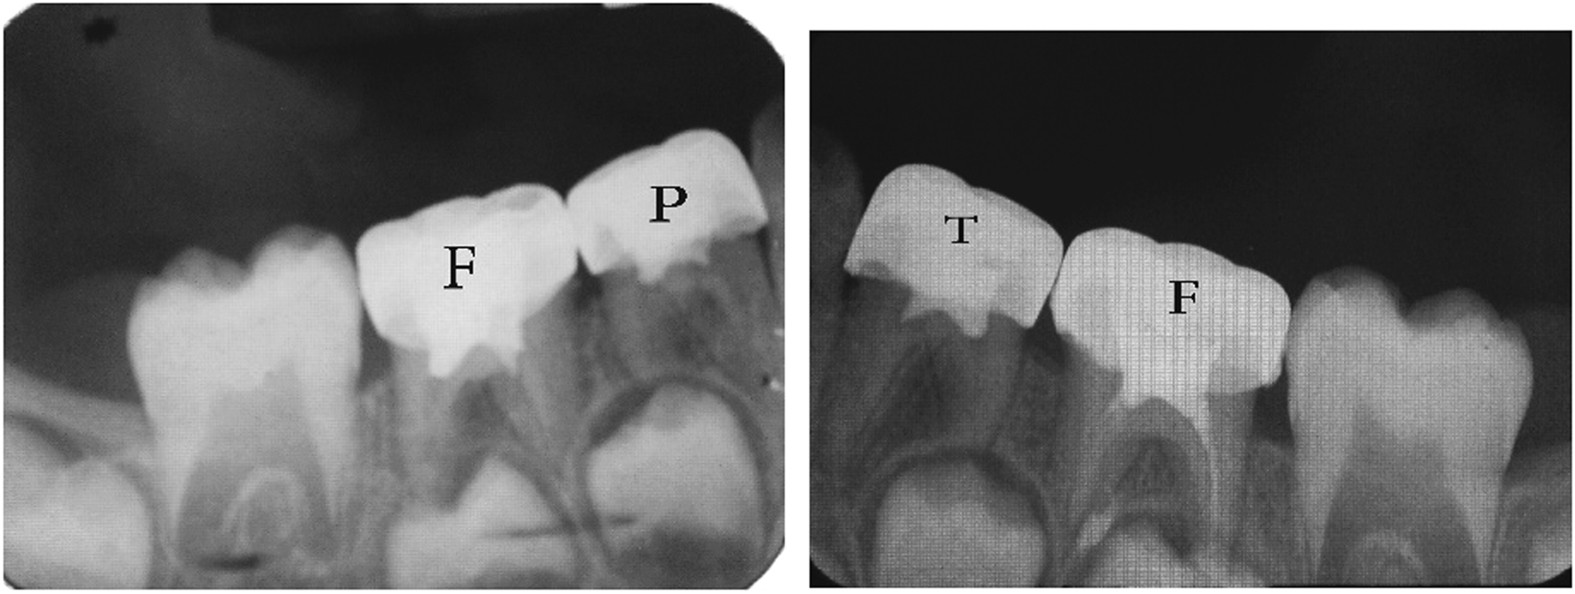

From: Clinical and radiographical evaluation of propolis and thymus vulgaris extracts compared with formocresol pulpotomy in human primary molars

Figure 4

Twelve months post operative.